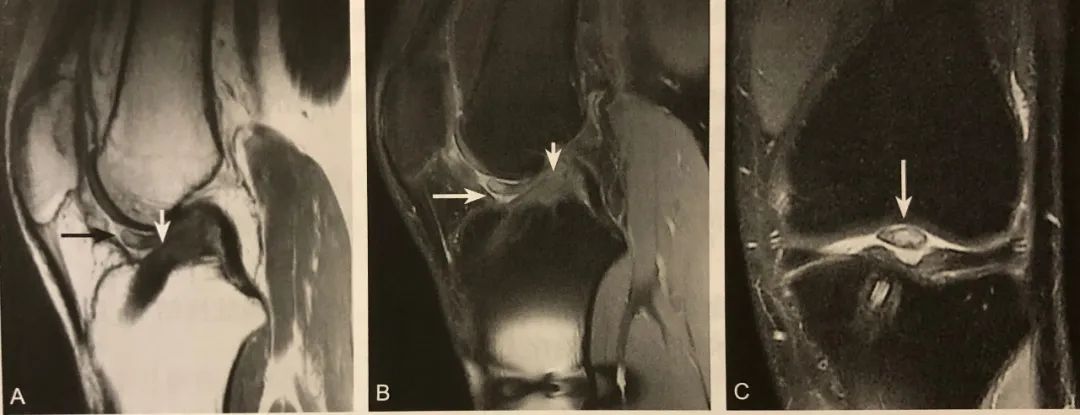

阅片要点:

1. 主要位于半月板前角边缘和关节囊之间;

2. 在膝关节侧位片或 MRI 矢状位观察;

3. T1WI 稍低或低信号;

4. T2WI 脂肪抑制呈高信号;

5. 增强扫描病变无强化或边缘轻度强化。